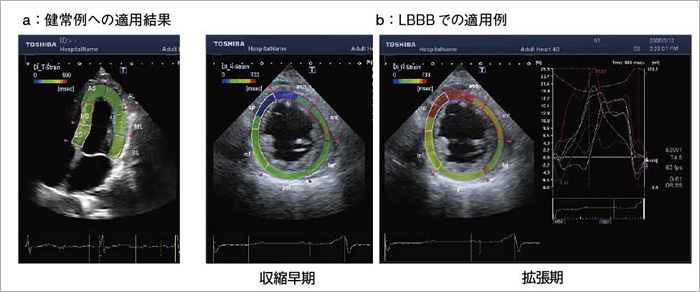

図8は,左脚ブロック(LBBB)症例に対する2DTの適用結果であり,収縮拡張運動のdyssynchronyを評価することができる。さらに,専用のパラメトリックイメージングとして,ストレインなどの壁運動パラメータが最大値に到達する時間をカラーコード化することができる(図9)。健常例(図10 a)に適用すれば,左室全体にわたって同一色(緑)で色付けされ,収縮のピークが同期していることが示される。一方,LBBBへの適用結果(図10 b)では,収縮早期では中隔の異常な早期収縮が青色で示され,収縮末期から拡張期にかけては,中隔の遅れた再度の収縮の動きが赤色として示されている。壁運動のdyssynchronyが明瞭に示されているのがわかる。

図10 スペックルトラッキングによるDyssynchrony Imaging(画像ご提供:筑波大学・瀬尾由広先生)